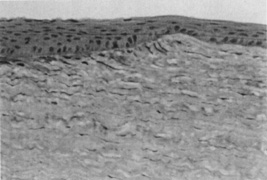

In 1983, Trokel and coworkers first reported the precise and controlled etching of the cornea by an argon–fluorine (ArF) excimer laser.28 Puliafito and colleagues compared the histopathologic effects of linear cornea ablation at 193 and 248 nm.29 Both studies found excellent preservation of normal corneal stromal microstructure adjacent to the ablation zone at 193 nm (Fig. 1). The adjacent cornea remained optically clear. High-power transmission electron microscopy showed a submicron zone of electron density immediately adjacent to the ablation only. Kerr-Muir and associates first described a pseudomembrane that appears to seal cells and cellular nuclei transected by the laser beam.30 In contrast, at 248 nm, disorganization of the collagen microstructure extended into the adjacent stroma for more than 10 νm.29 The cornea immediately adjacent to the ablation showed a loss of transparency, which was indicative of thermal injury. Further, a study by Peyman and associates31 showed a significant coagulative effect from 308-nm excimer laser radiation with induced corneal necrosis, stromal opacification, and endothelial cell damage.

Fig. 1. Light micrograph of a 193-nm, slit-like ablation in a bovine cornea. Dosage parameters: 20,000 pulses, 50 Hz, 125 mJ/cm2 per pulse, with a 10 νm mask (original magnification ×214). (Puliafito CA, Steinert RF, Deutsch TF, et al: Excimer laser ablation of the cornea and lens: Experimental studies. Ophthalmology 92:741, 1985)